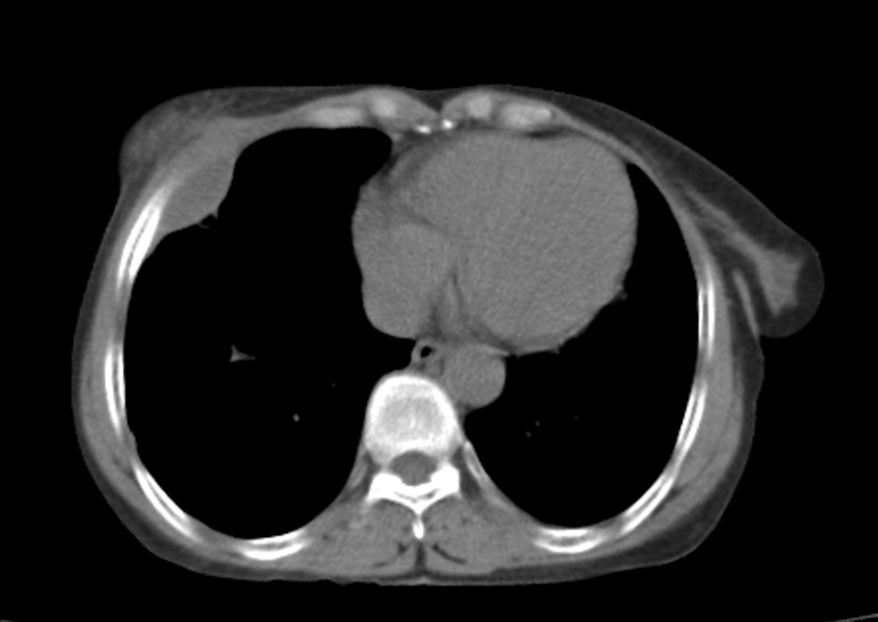

标题: CT21609:右乳包块1年,请各位讨论分析一下,乳腺CA, [打印本页]

标题: CT21609:右乳包块1年,请各位讨论分析一下,乳腺CA,

考虑---右乳癌并胸壁、肋骨、双肺转移。

考虑乳腺癌侵犯肋骨、胸壁及两肺转移可能性大。

右乳癌并胸壁、肋骨、双肺转移。

考虑右侧乳腺癌侵犯肋骨、胸壁及两肺转移。

支持考虑---右乳癌并胸壁、肋骨、双肺转移。

考虑右侧乳腺癌侵犯肋骨、胸壁及两肺转移可能。

考虑右侧乳癌并胸壁、肋骨及双肺多发性转移。